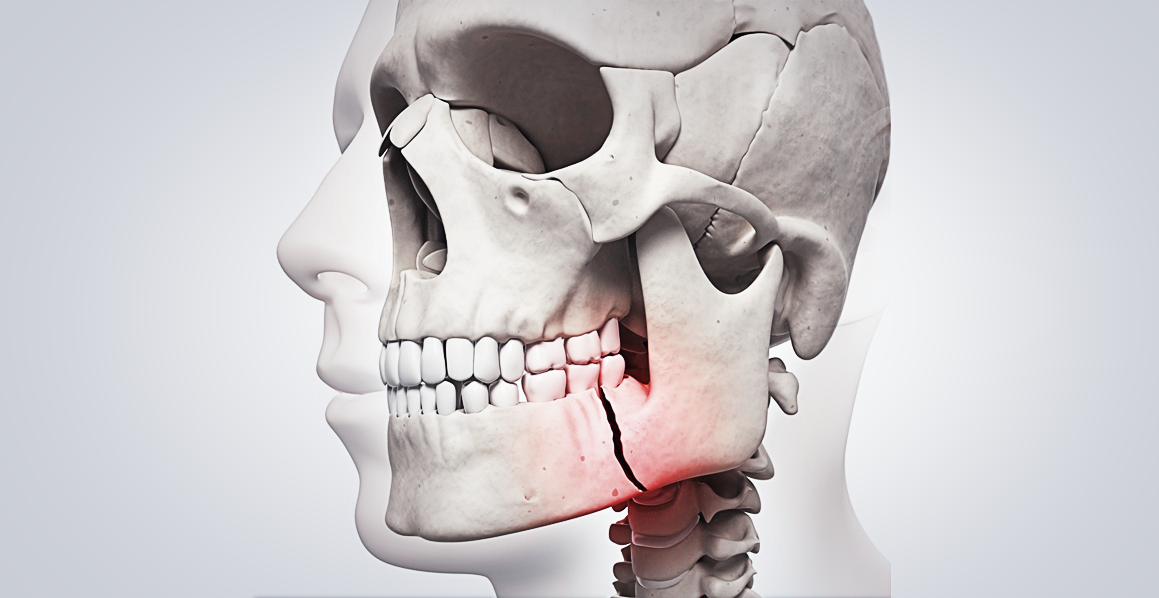

Traumatismo

Lesões traumáticas na região orofacial podem comprometer dentes, tecidos moles e estruturas ósseas, exigindo abordagem emergencial para minimizar sequelas funcionais e estéticas.

Avulsões dentárias requerem reimplante imediato e estabilização por meio de contenção semirrígida, enquanto fraturas maxilofaciais podem necessitar de imobilização cirúrgica para restaurar a integridade estrutural.

Além do impacto local, traumatismos extensos podem estar associados a fraturas cranianas e lesões neurológicas, sendo imprescindível uma avaliação multidisciplinar em casos de alta complexidade.